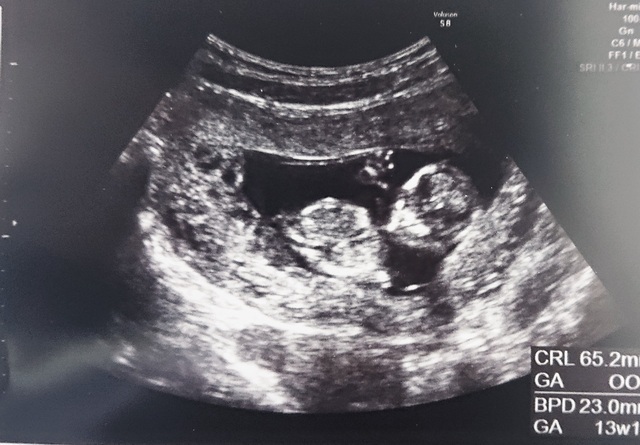

12週6日(12w6d・性別不明・双子)|ちびのすけ さん(37歳)

エコー写真撮影時のエピソード:

およそ1ヶ月前に双子と診断されて初めは戸惑って不安に陥ったけど、今はパパと息子とツインズが生まれて来てくれるのを心待ちにしています。

両親は思いもよらない報告にびっくりしてますが、まずは無事に産まれてきてくれることを願ってくれてます。